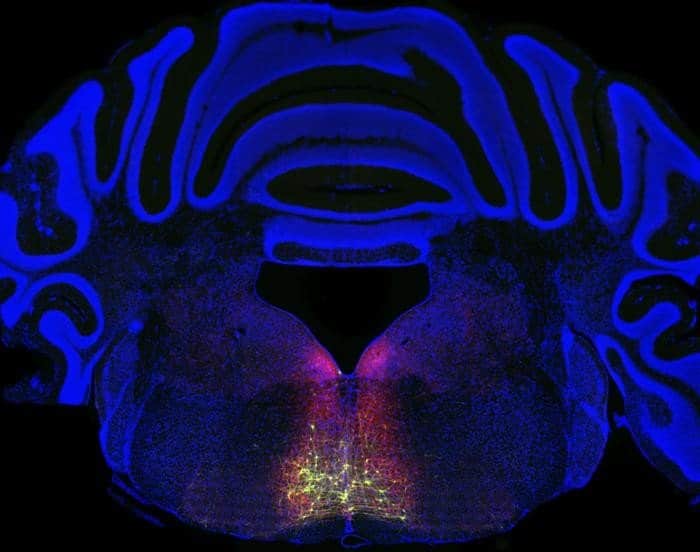

To find that full circuit, Chen’s team worked backwards from a group of neurons found in the RVM known to be involved in pain sensitization. Building on previous genetic methods, they tagged neurons along the chronic pain circuit with a fluorescent protein.

The glowing trail that resulted revealed a previously unknown circuit loop originating in the spinal cord, then linking to the thalamus, the cortex, the brainstem (where the RVM is located), and back to the spinal cord.

Image: The image is credited to Courtesy Xiaoke Chen/Stanford University

“Deconstruction of a spino-brain–spinal cord circuit that drives chronic pain” by Qian Wang (王倩), Joo Han Lee (이주한), Gregory Nachtrab, Yuan Yuan, Lei Yuan, Wei Qi, Manuel A. Mohr, Jing Xiong, Mark A. Horowitz & Xiaoke Chen (陈晓科). Nature

Here we report a circuit loop that extends from the spinal cord to the ventral posterolateral thalamus and posterior complex of the thalamus, proceeds to the primary somatosensory cortex and returns to the spinal cord via the lateral superior colliculus, which in turn connects to μ-opioid-receptor-expressing RVMSC neurons.